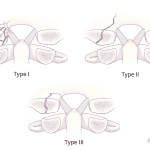

- Remember that the alar ligaments attach to the occipital condyle. Displaced avulsion fractures are considered unstable injuries concerning for underlying ligament injury, and while you do not need to know the surgical classification schemes, make sure to mention whether or not these fractures are displaced